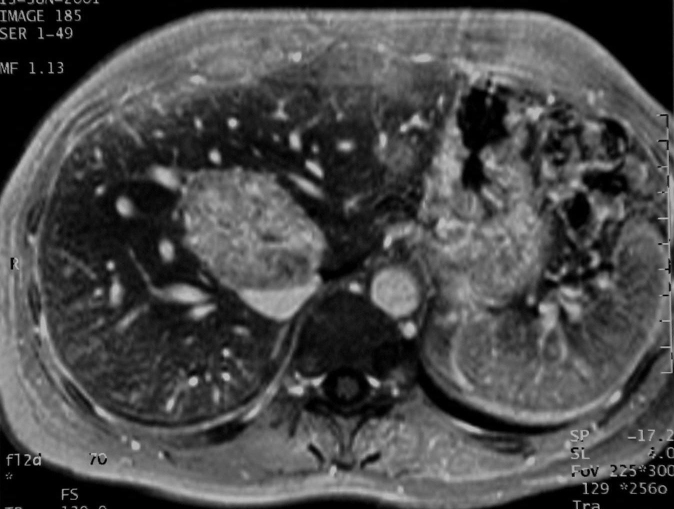

La masse est située dans la convergence des veines sus hépatiques. Elle est nettement hyper T2 et légèrement hypo T1, un peu hétérogène. Elle se rehausse franchement après injection de gadolinium. Il n'y a pas de capsule visible. les contours sont finement bosselés. Cet aspect est assez typique d'une HNF télangectasique. Un examen avec Endorem a été réalisé. Bien qu'ellle fixe l'endorem dans les mémés proportion que le foie avoisinant (Le T1 a diminué de 25%dans le foie et la lésion) Nid-C7.jpgelle est beaucoup mieux visible ainsi que sa structure finement hétérogène. Aucune capsule n'est visible. Le diagnostic a été confirmé par biopsie.